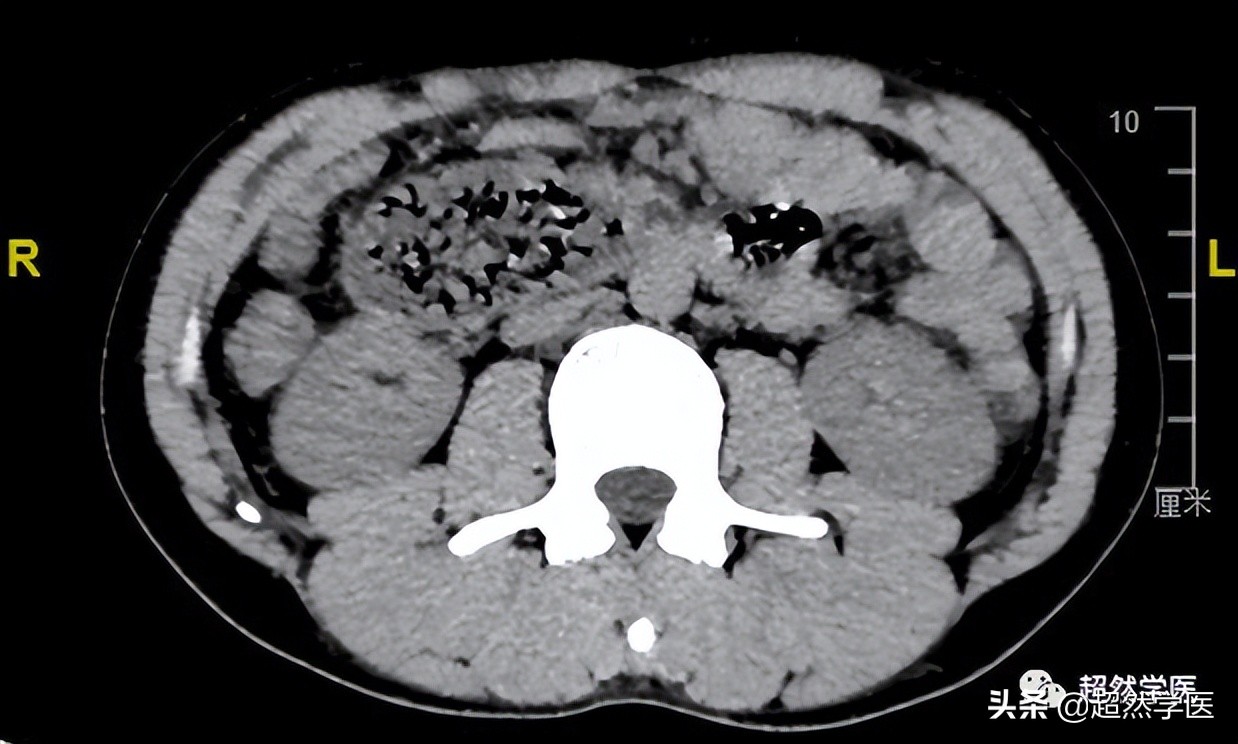

腹部CT的影像非常典型:

十二指肠近端扩张明显,而中间部分极为狭窄,约0.5cm左右

胃腔大量胃液。没有明显的胃肠型体征和其他部位的梗阻或结石征象。

综合以上资料,目前在判断SMA综合征上,还是证据不足,因为,没有明显看到动脉夹角小于25度以下以及十二指肠受SMA压迫。